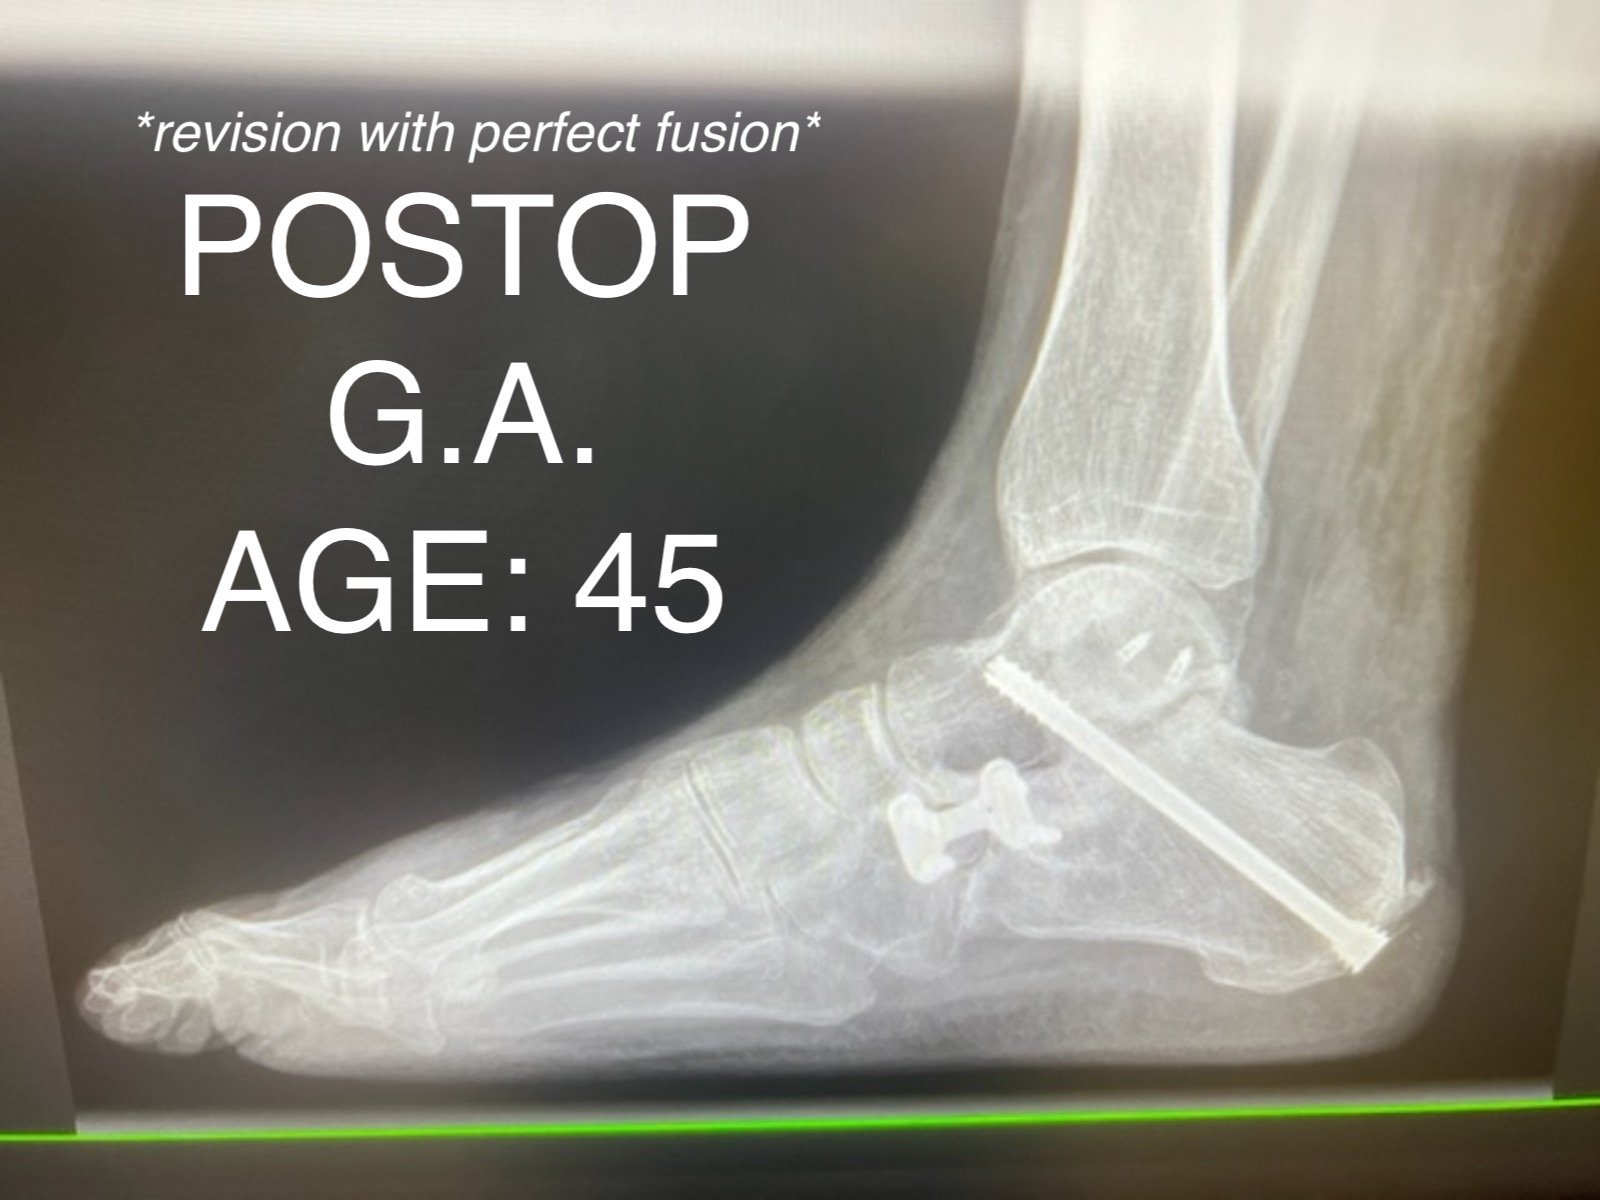

ANKLE FUSION